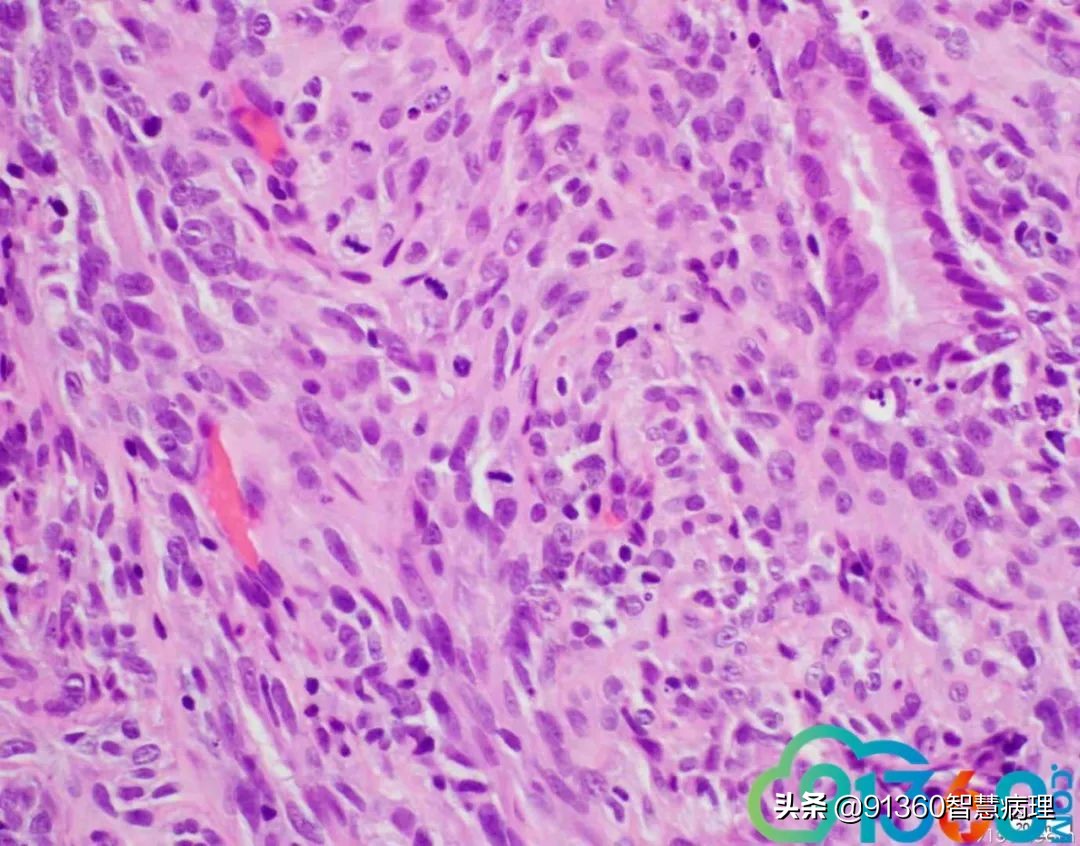

邢德印 Desmin -Sarcomatoid carcinoma; spindle cell carcinoma 石岩 @邢德印(妇科病理) 好例子 邢德印 以前没见过这么明显的,太肉瘤样了 任永昌 @邢德印(妇科病理) 赞 郭晓静 @邢德印(妇科病理) 我偏向猜的答案也是这个,。谢谢分享! 王昀 @邢德印(妇科病理) 好例子,没见过这么弥漫肉瘤样的,回过头来看,好像还是有点结构的样子

邢德印 @王昀 301 圈里的是mitosis 任永昌 @邢德印(妇科病理) @王昀 301 实际上,上边这个腺体有异型,核过于大。

王昀 哦,我说那个裂隙,有点像腺的结构 邢德印 @临沂市中心医院任永昌 @王昀 301 腺体其实是entrapped,正常的腺体 王昀 我是想起乳腺的化生性癌,所以想看看有没有腺和梭形细胞过渡移行的地方,能找点线索,可能是知道答案后开始想象了,这个可能是假腺